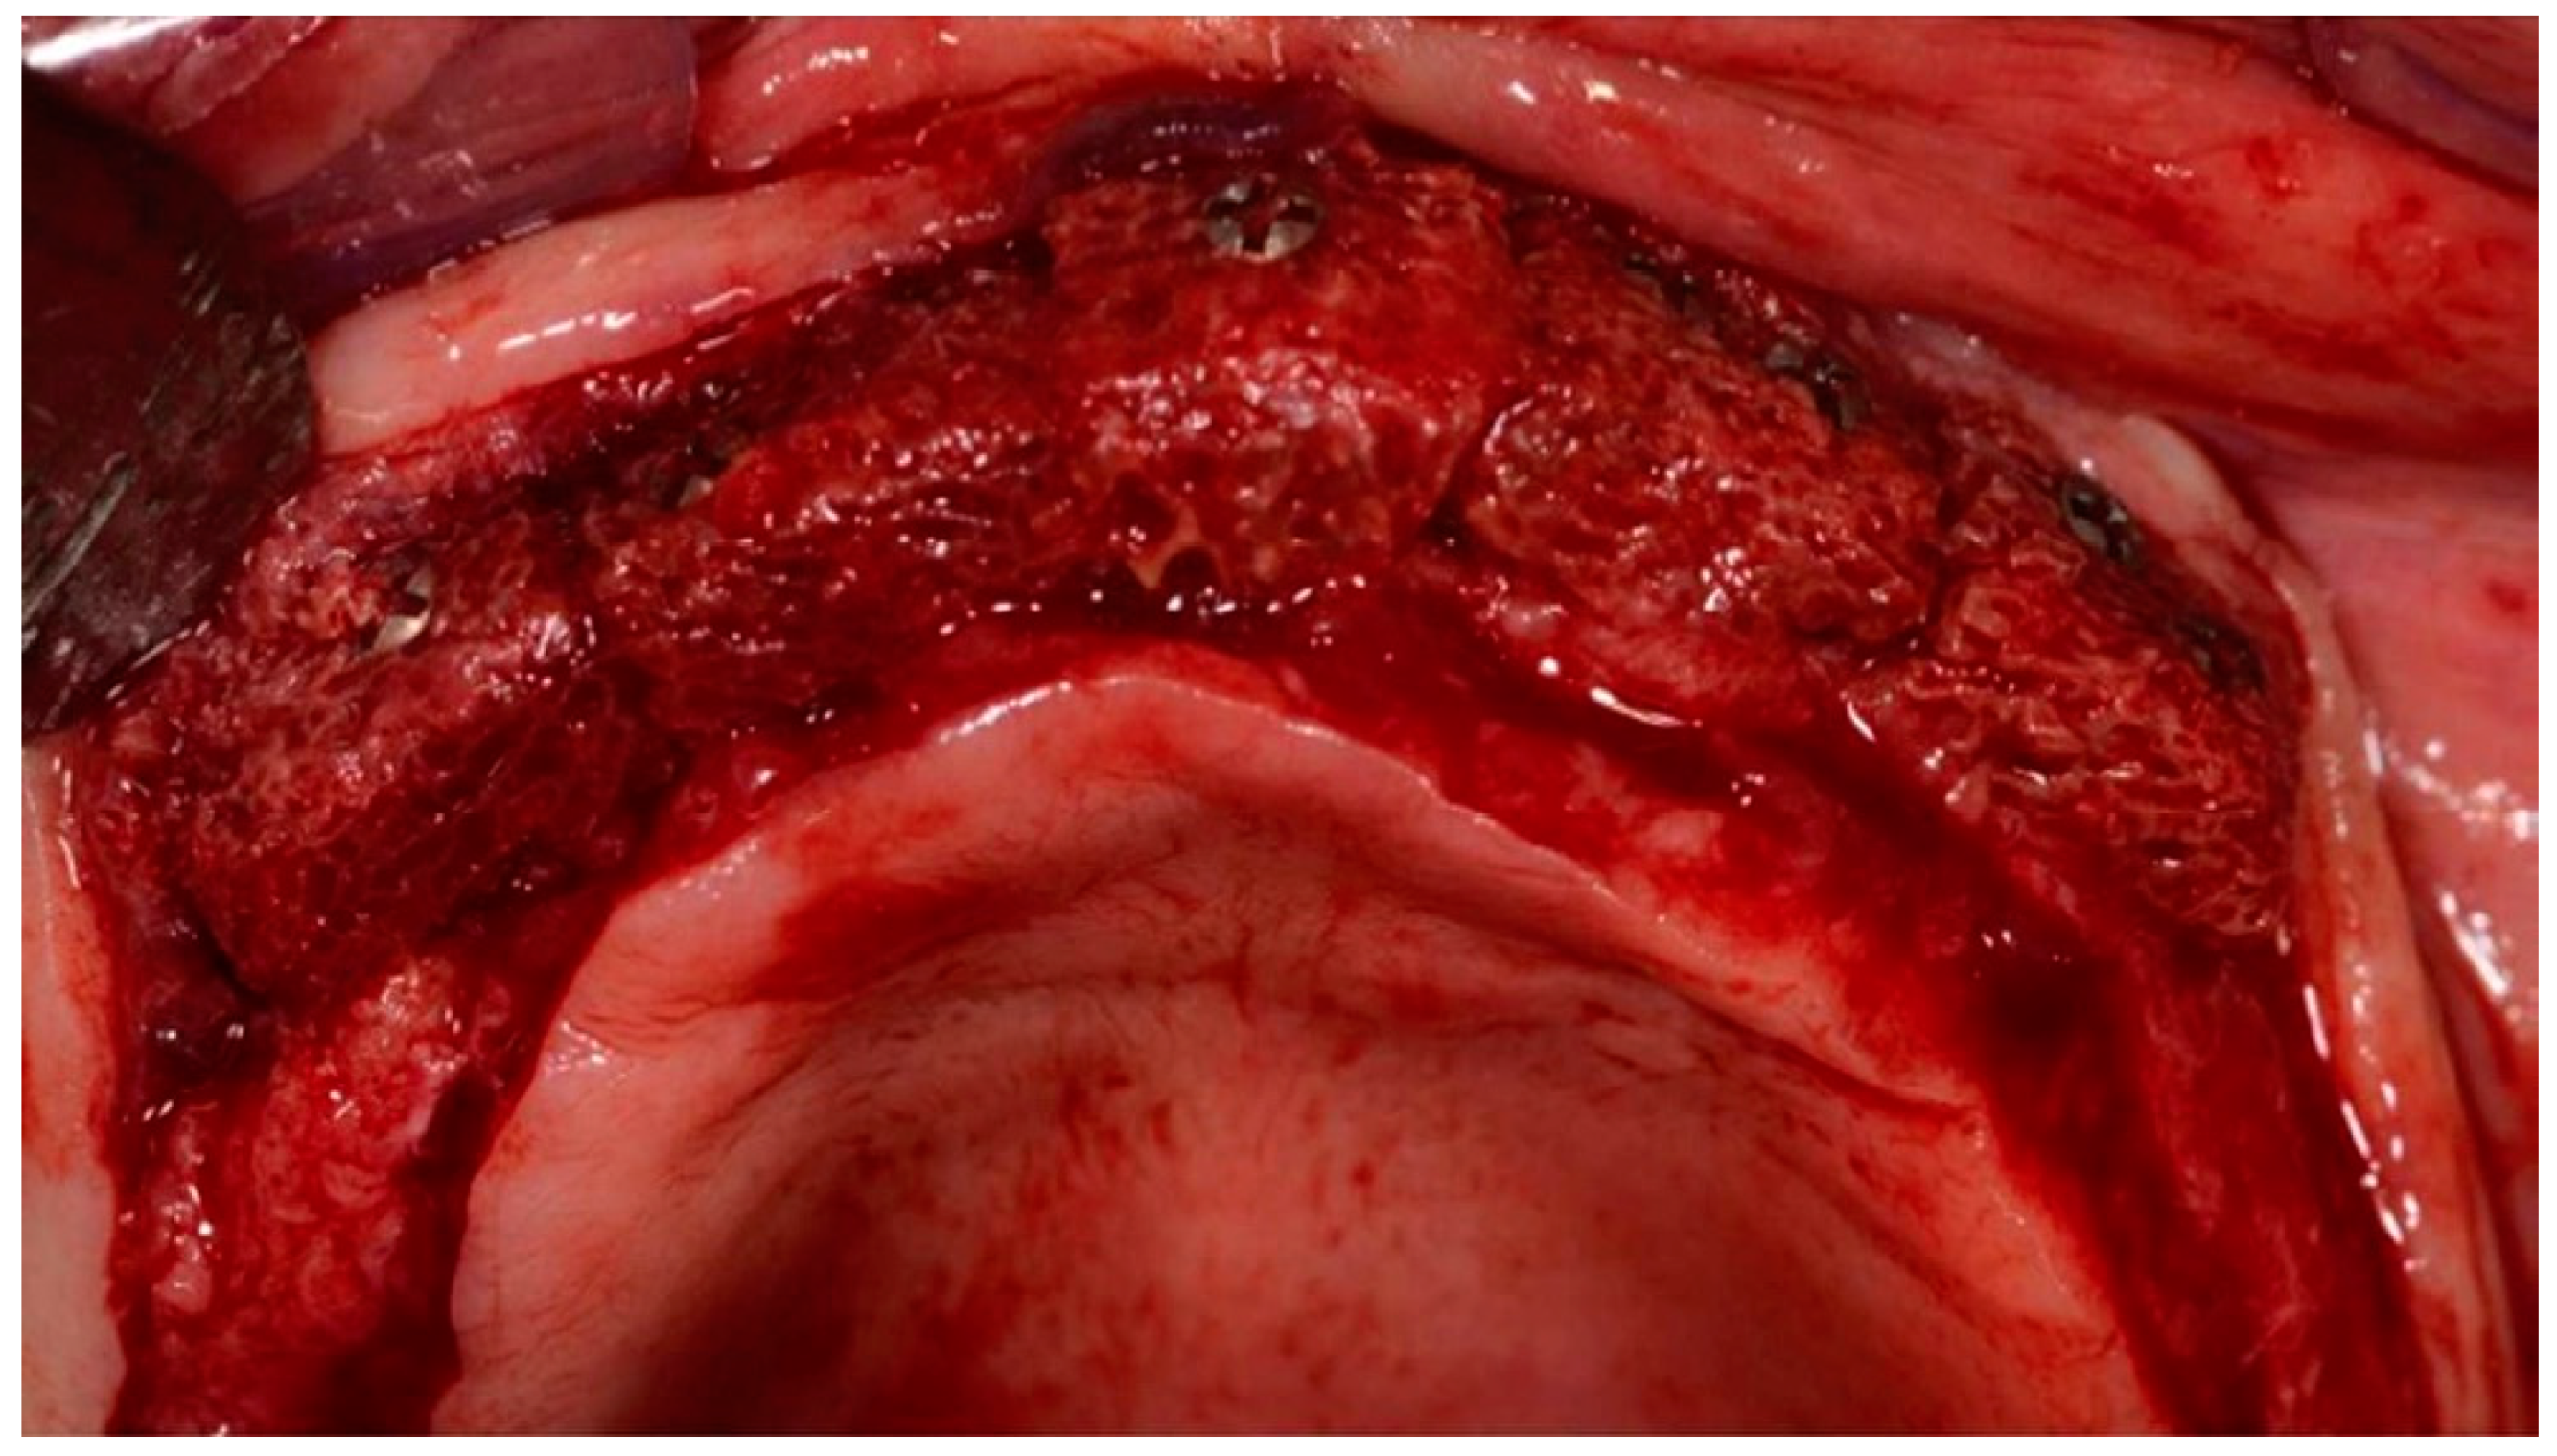

2.2. Association of the Bone Marrow Aspirate Concentrate to the Xenograft Blocks

2.3. Surgical Technique for Bone Grafting